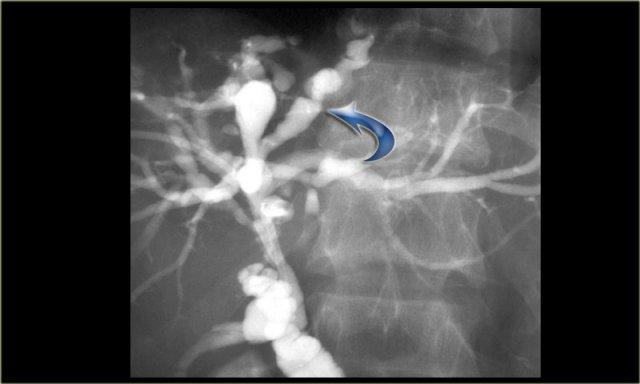

ERCP: Bệnh Caroli với giãn ống mật trong gan nặng. Không có tắc nghẽn. Giãn nhẹ ống mật chủ do viêm đường mật

Chụp đường mật đóng vai trò quan trọng trong quá trình đánh giá những bệnh nhân này, vì cần phải loại trừ tình trạng tắc nghẽn.

Điều này có thể được thực hiện bằng MRCP hoặc ERCP, như được minh họa bên trái.

Không có dấu hiệu tắc nghẽn.

Giãn nhẹ ống mật chủ là kết quả của viêm đường mật.

Có giãn khu trú xen kẽ với các đoạn hẹp của ống mật tại phân thùy IV (mũi tên).

Các ống mật còn lại và ống mật chủ bình thường.